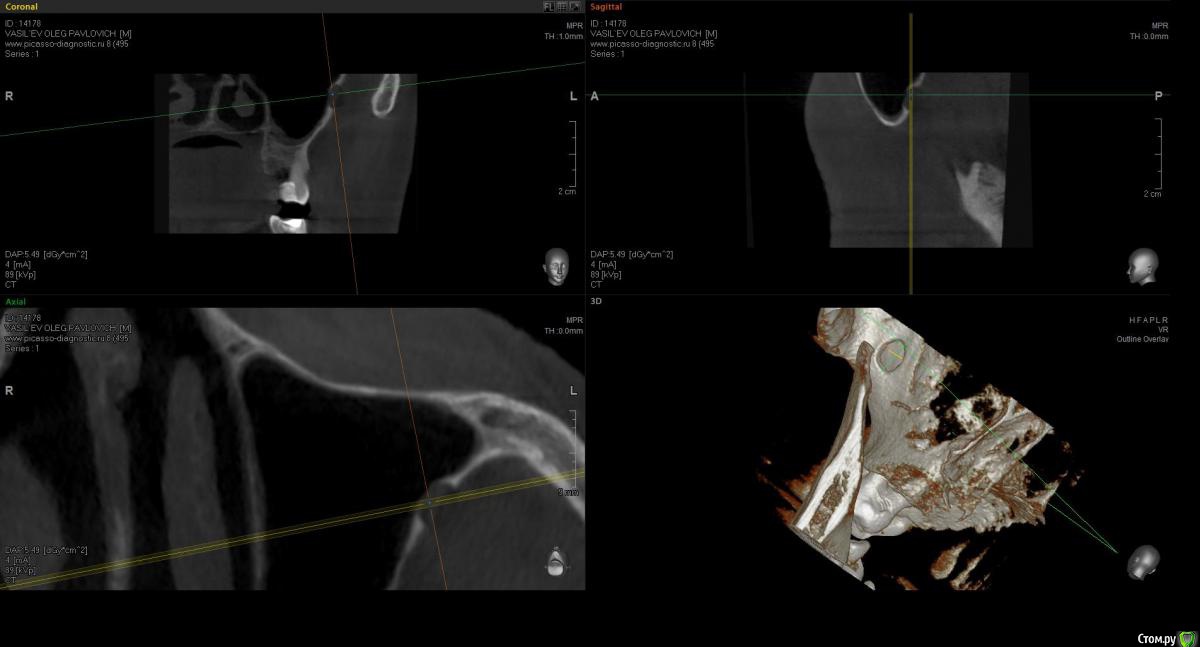

sugaka30 Опубликовано 22 января, 2017 Поделиться Опубликовано 22 января, 2017 Что не так с моей челюстью? Озноб слабость Температура в районе 37 Ссылка на комментарий

red_butler Опубликовано 22 января, 2017 Поделиться Опубликовано 22 января, 2017 Данные срезы не информативны. Не плодите темы, продолжайте в основной. Ссылка на комментарий